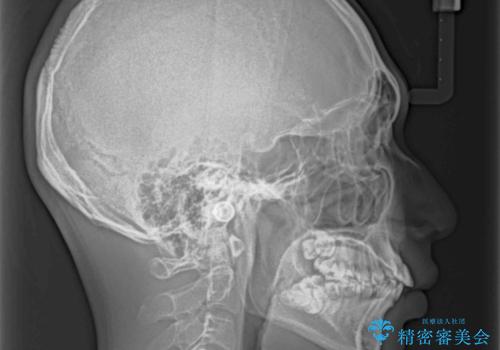

- 前歯の叢生と八重歯を気にして来院された患者様です。

叢生が強く、奥歯の咬合も左右差が大きかったため、上下左右4本を抜歯して、ワイヤー矯正を行うこととしました。

奥歯の咬み合わせを改善したいため、治療期間が長くなりましたが、患者様には辛抱強くお付き合いいただきました。

上下の正中を合わせることもでき、患者様には大変満足していただきました。